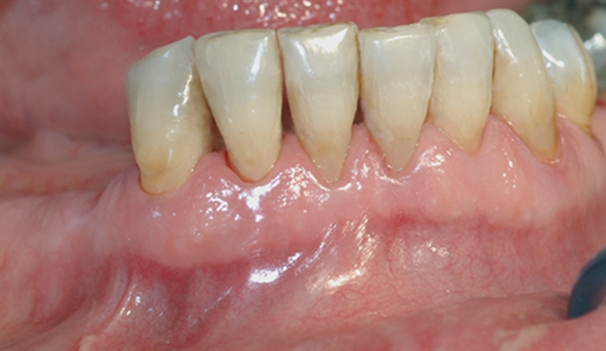

perio stor 6

Bildet viser et nærbilde av tennene i underkjeven med tannsten og misfarging.

perio stor 7

Bildet viser forholdene i underkjeven etter at tannsten og misfarging er fjernet